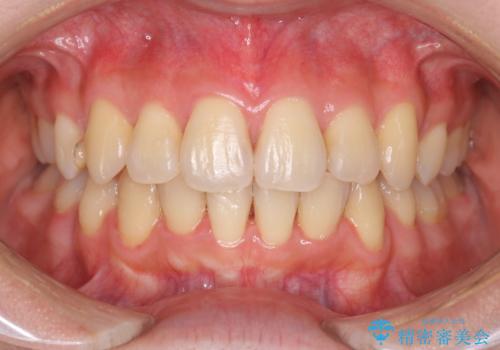

30代女性 前歯のがたつき